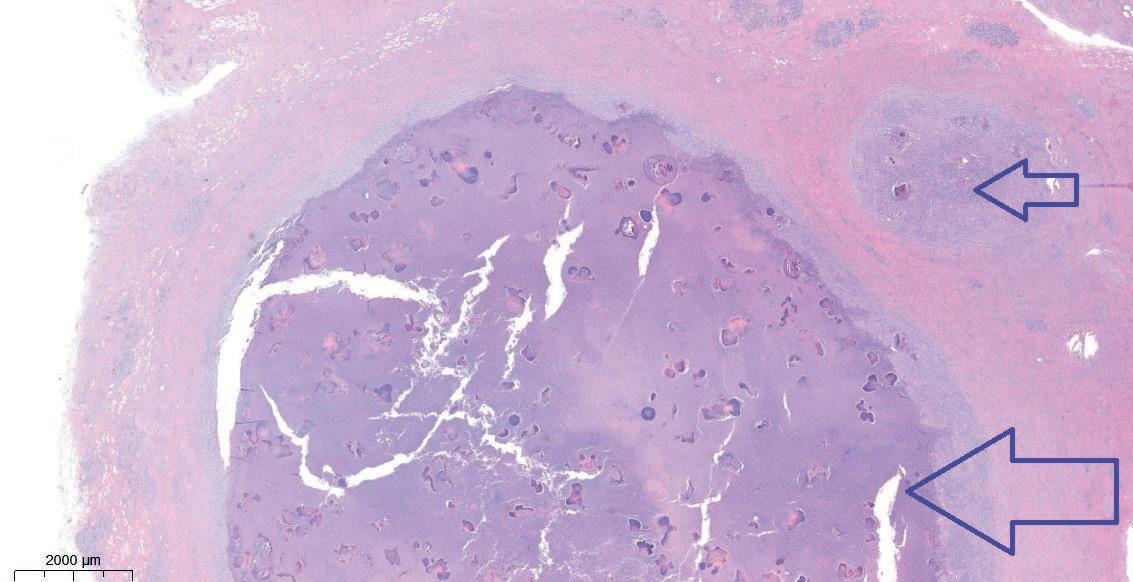

The mammary skin of affected sows had red pustules developing to firm nodules of 1-2 cm in diameter (Fig 1). Some pustules resolve, others increase in size. During lactation, pustules can ulcerate and develop draining tracts. Clinically, the presumptive diagnosis of 'Actinomycosis' was made, but lesions do not resemble textbook cases. Histologically, lesions consist of multifocal granulomatous to pyogranulomatous inflammatory processes in the dermis and subcutis (Fig 2 and Fig 3). The central necrotic debris had an intense neutrophilic inflammatory infiltrate, accompanied by radially arranged deeply eosinophilic amorphous protein, known as the 'Splendore Hoeppli' phenomenon, around large bacterial colonies (Fig 3, 4 and 5). Culture revealed two strains of Staphylococcus aureus with different antimicrobial susceptibility, as well as Streptococcus dysgalactiae ssp. dysgalactiae. Anaerobic culture revealed absence of growth.

Fig 2.: Overview image (HE staining) of dermal pyogranuloma with a fibrous capsule and central purulent debris (large arrow) and smaller satellite granulomas (small arrow)